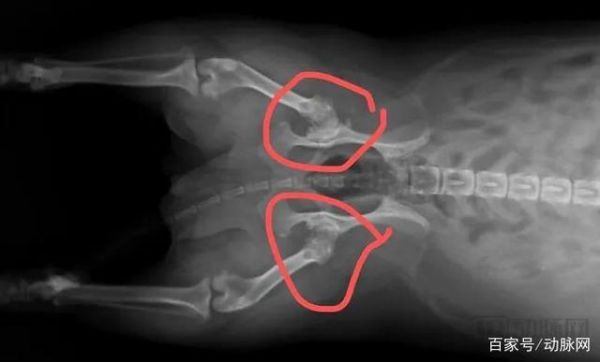

从那时开始,刘小姐开始频繁地带Tony前往附近的宠物医院进行检查,陆陆续续给小狗做了全身X光、心脏超声等影像学检查,这才得知Tony的髋关节已经严重磨损,心脏也比正常的大了20%。一个月折腾下来,影像检查加上各类治疗药物总算让Tony的生活恢复了正常,但前前后后花了刘小姐近3000块钱。

Tony的髋关节X光影像